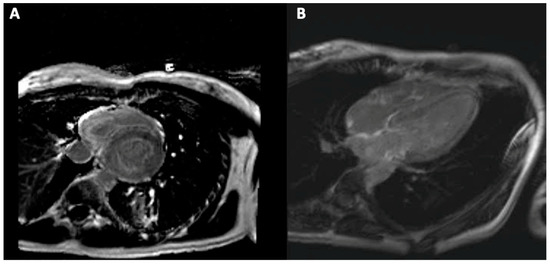

5. Cardiac Magnetic Resonance Imaging

5.1. Cardiac Magnetic Resonance Imaging in Amyloidosis

5.2. Cardiac Magnetic Resonance Imaging in Sarcoidosis

5.3. Cardiac Magnetic Resonance Imaging in Hemochromatosis